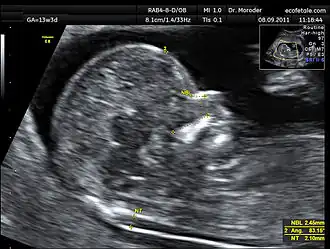

Enlarged NT and absent nasal bone in a fetus at 11 weeks with Down syndrome

In another study values of 79.6% and 2.7% for the combined screening were then improved with the addition of second trimester ultrasound scanning to 89.7% and 4.2% respectively.[13] A further study reported detection of 88% for trisomy 21 (Down syndrome) and 75% for trisomy 18 (Edwards syndrome), with a 3.3% false-positive rate.[14] Finally, using the additional ultrasound feature of an absent nasal bone can further increase detection rates for Down syndrome to more than 95%.[15]